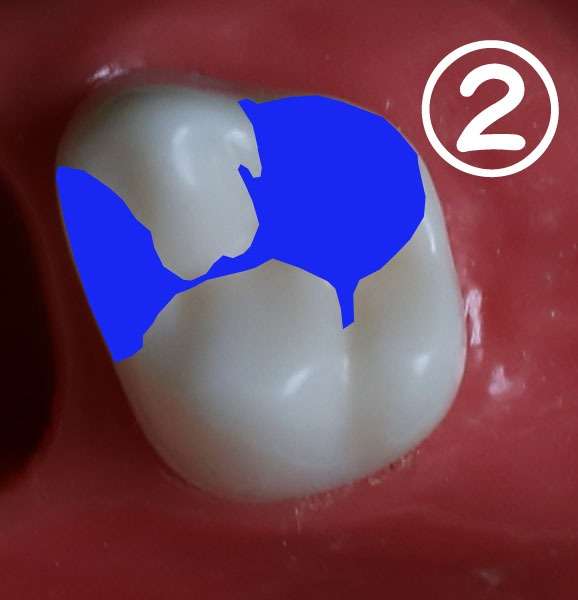

CAD/CAMインレーの適応例

図のように噛み合わせの山の部分まで虫歯が及ぶ場合に

今までのコンポジットレジン修復やレジンインレーでは耐磨耗性に劣るため

どうしても金属で咬合の安定を図ることが多かったのですが、

CAD/CAMインレーは強度が得られるためこういったむし歯でも金属にならずに済むようになります